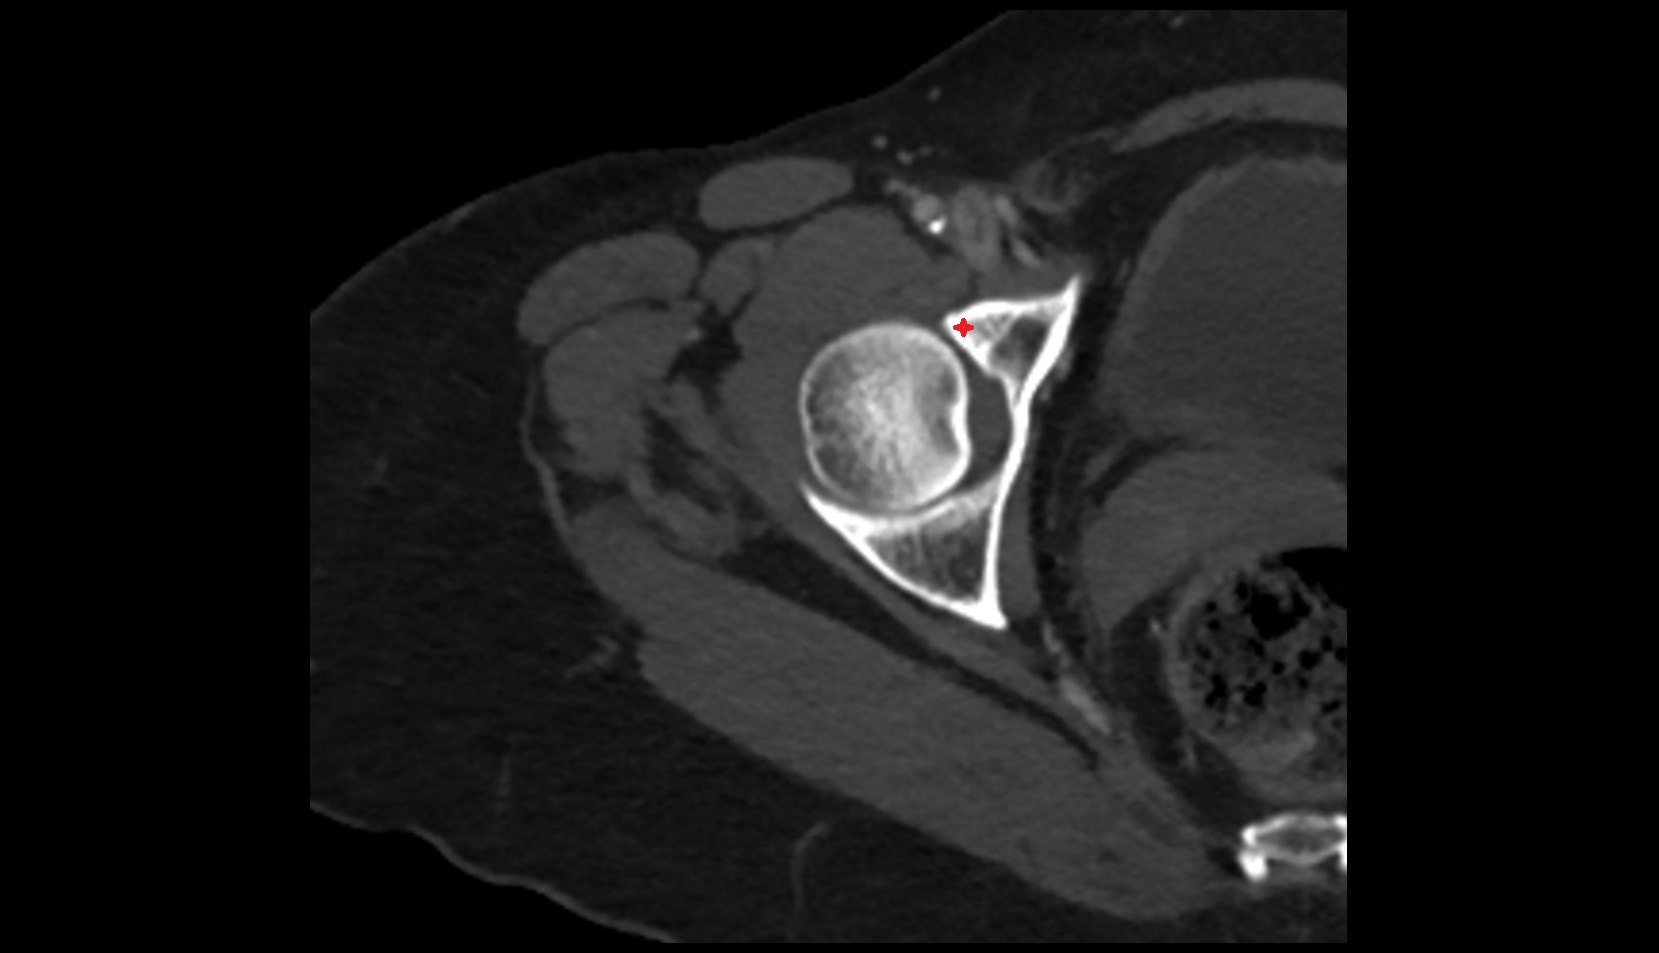

- Femoral artery

- Head of femur